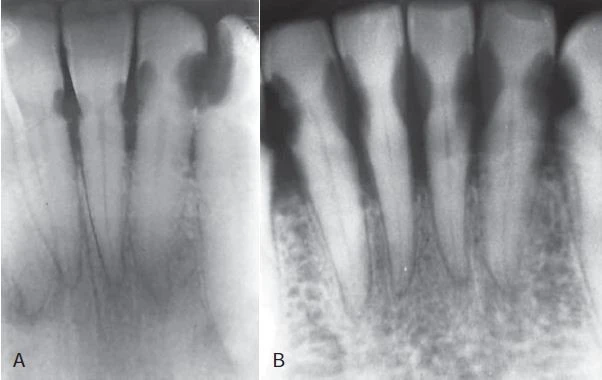

ĐA SÂU RĂNG

Sâu răng phá huỷ răng tiến triển nhanh và rầm rộ thường được gọi là đa sâu răng và thường thấy ở trẻ em có chế độ dinh dưỡng không đầy đủ và thói quen vệ sinh răng miệng kém. Tuy nhiên, tình trạng này ngày càng hiếm do việc bổ sung fluor trong nguồn nước, sử dụng fluor tại chỗ và nâng cao kiến thức về dinh dưỡng cũng như vệ sinh răng miệng. Đa sâu răng có thể thấy ở những người bị chứng khô miệng. X quang của những cá nhân này cho thấy hình ảnh sâu răng phá tuỷ trầm trọng, tiến triển, đặc biệt là những răng trước hàm dưới.

THỦ THUẬT SAU KHI XẠ TRỊ

Những bệnh nhân được điều trị xạ trị ở vùng đầu và cổ có thể mất chức năng tuyến nước bọt, dẫn đến khô miệng, thay đổi hệ khuẩn chí vùng miệng và có khả năng thay đổi nội tại cấu trúc răng. Nếu không điều trị, điều này có thể gây nên phá huỷ răng hàng loạt, còn gọi là đa sâu răng. Thông thường, sự phá huỷ bắt đầu tại vùng cổ răng và có thể tiến triển nhanh vòng quanh thân răng, dẫn đến mất toàn bộ thân răng và chỉ còn lại mảnh chân răng trên cung hàm. Hình ảnh X quang của sâu răng do xạ trị có những nét đặc trưng: bóng thấu quang nằm ở vùng cổ răng, hầu hết rõ nét ở mặt gần và mặt xa. Hiện diện những biến thể độ sâu của tổn thương phá huỷ, nhưng thường có sự thống nhất trong một vùng trong miệng. Hình bên dưới biểu thị một dẫn chứng của sâu răng ở bệnh nhân bị khô miệng sau khi thực hiện liệu pháp xạ trị ung thư vùng đầu và cổ. Sử dụng liệu pháp fluor tại chỗ như là dung dịch tái khoáng hoá và vệ sinh răng miệng kỹ càng có thể làm giảm đáng kể những tác hại của xạ trị lên răng do khô miệng.

Hình 19. Sâu răng sau xạ trị